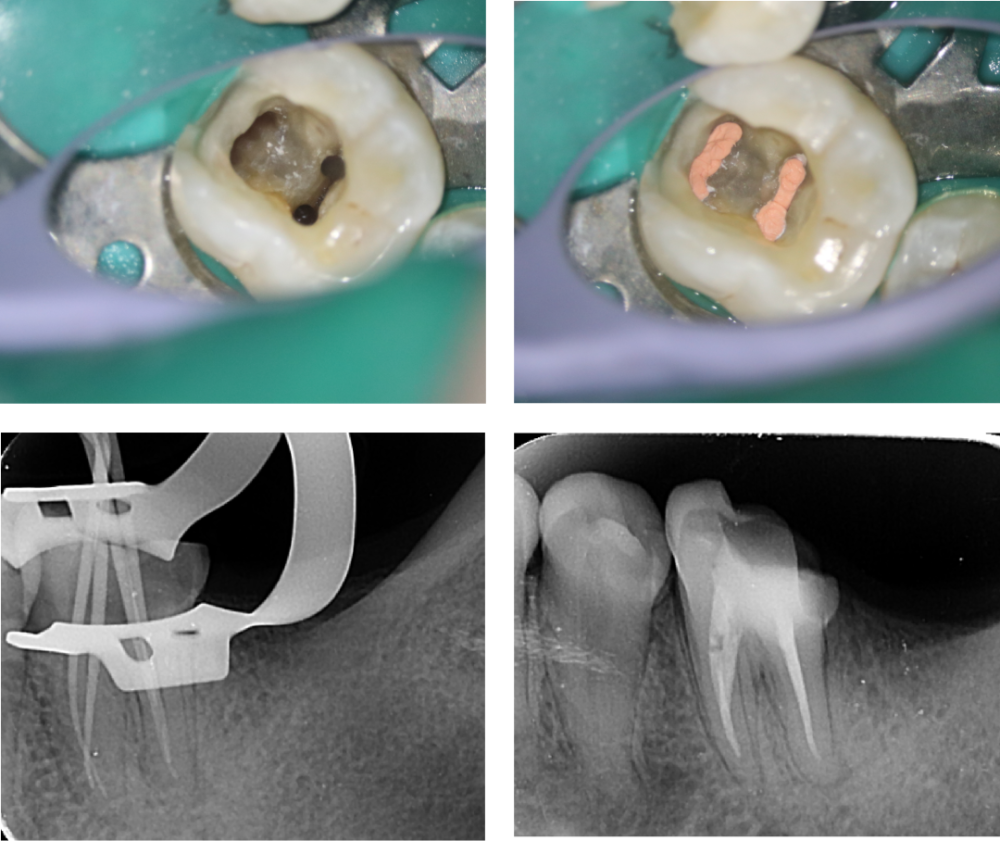

牙医必备后牙多颗龋坏根管治疗嵌体修复